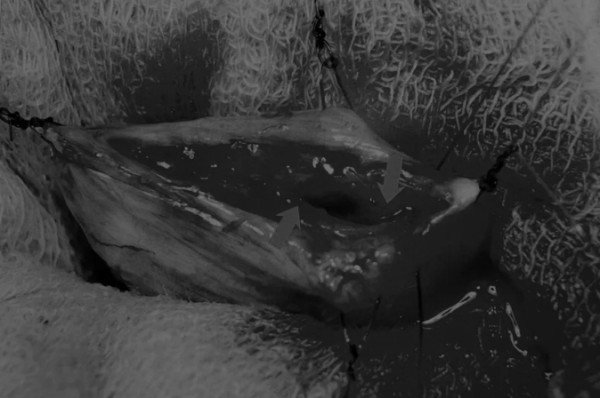

在中线开腹手术后,确定膀胱,将其取出并隔离(图1)。为了使膀胱持续暴露,可在膀胱中线两侧各放置一根固定缝线(图2)。

图1 将膀胱从腹腔中取出,用无菌外科敷料隔离。为了防止膀胱滑入腹部,可在膀胱顶部放置一根固定缝线,由助手通过止血钳夹住固定缝线做持续牵引

在牵引缝线之间选择血管扩张较差的区域用手术刀切开膀胱壁(图3)。在牵引缝合线之间用手术刀在血管不良的区域做切口。切开膀胱壁后,膀胱内的手术可按手术方案实施,例如取出结石(图4)。

图3 避开主要的膀胱血管,做一个尽可能小的切口